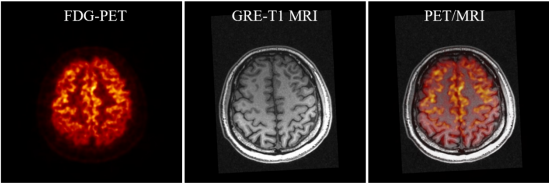

SIAT bPET和联影uMR790 3T磁共振成像系统上同时获得的人脑PET/MRI图像